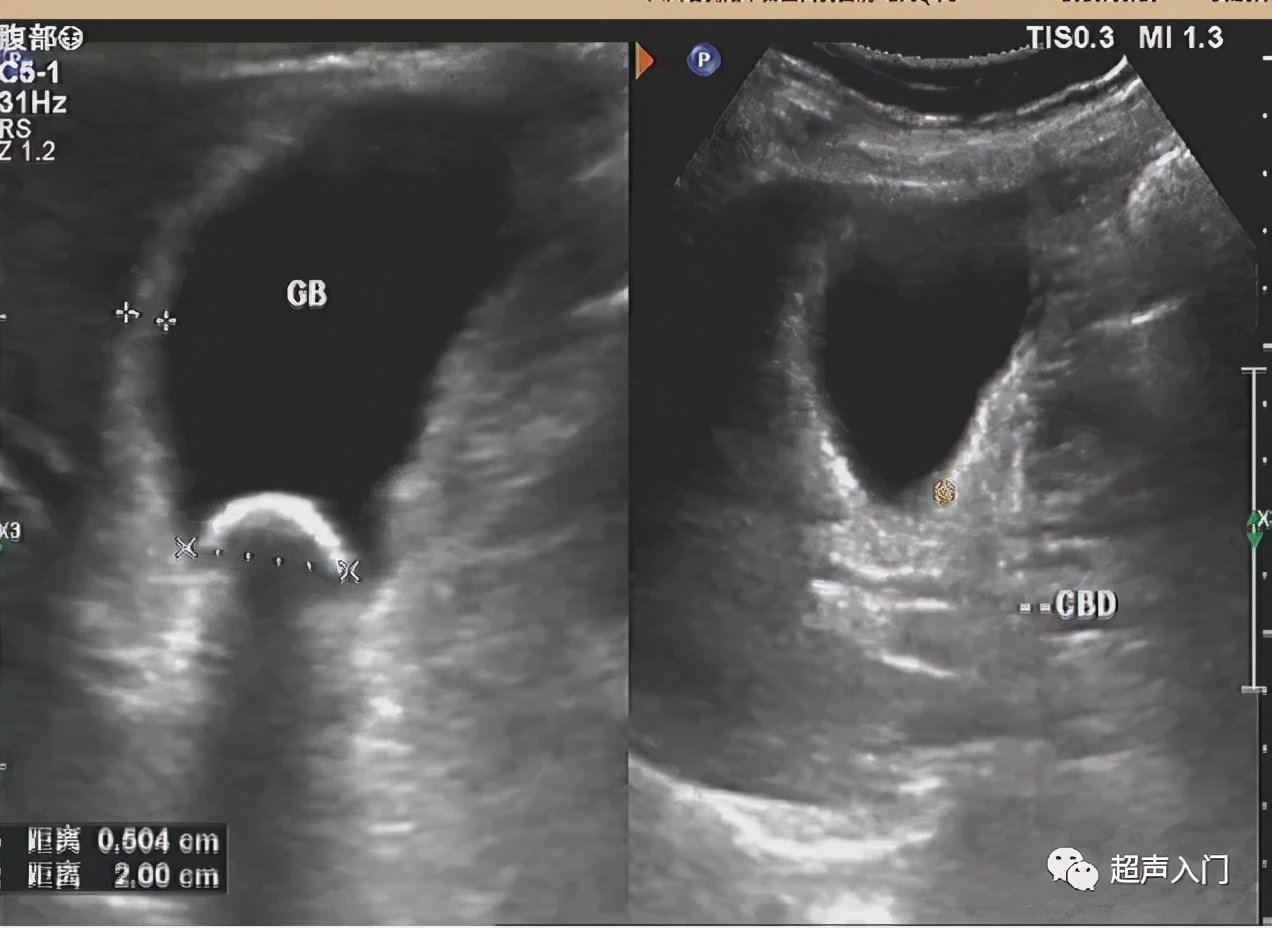

5、多伴有胆囊结石,往往嵌顿于胆囊颈管部。

胆囊英汉对照: 胆囊(gallbladder) 缩写:GB

胆囊正常值: 长径≤9.0cm,横径≤4.0cm,胆囊壁厚度≤0.3cm,儿童胆囊长径<7cm,横径<3.5cm